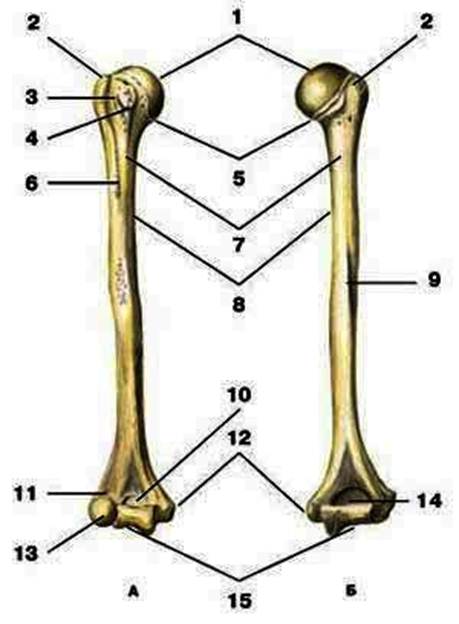

S: Цифра 1 обозначает головка плечевой кости.

S: Число 15 обозначает блок плечевой кости.

S: Цифра 5 указывает на хирургическая шейка плечевой кости.

S: Число 10 обозначает венечная ямка плечевой кости.

S: Число 14 указывает на локтевая ямка плечевой кости.

S: Цифра 9 указывает на борозда лучевого нерва плечевой кости.

S: Число 12 обозначает медиальный надмыщелок плечевой кости.

S: Стрелка указывает на большой бугорок плечевой кости.

S: Стрелка указывает на малый бугорок плечевой кости.